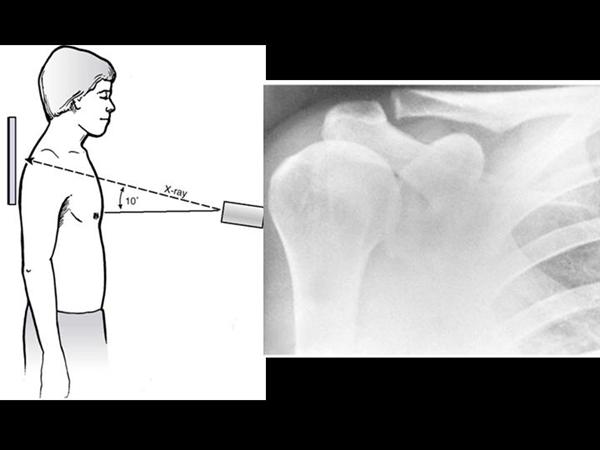

1. shoulder AP

glenohumeral joint space, DJD

2. True shoulder AP

Glenohumeral joint space, DJD, and proximal migration of humerus